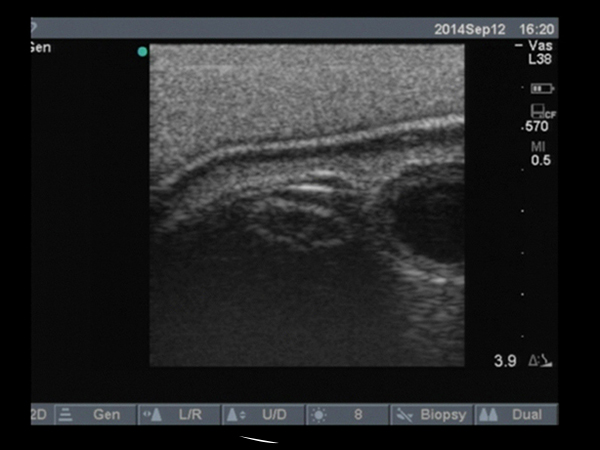

The Regional Anesthesia Femoral Trainer with SmarTissue allows skills practice for femoral nerve blocks with ultrasound compatible tissue. This trainer allows ultrasound practice with visualization of the most clinically relevant femoral anatomy and needle tip to ensure proper manipulation, placement, and proximity to the nerves. The trainer consists of a body form and replaceable tissue, each embedded with SmarTissue technology, allowing the system to connect with any PC to provide needle-to-nerve visuals and audio verification of proper technique.

• Ultrasound is compatible for guidance during needle insertion.

• SmarTissue software interprets unique signals, showing orange when in contact and red when penetrating the nerve.